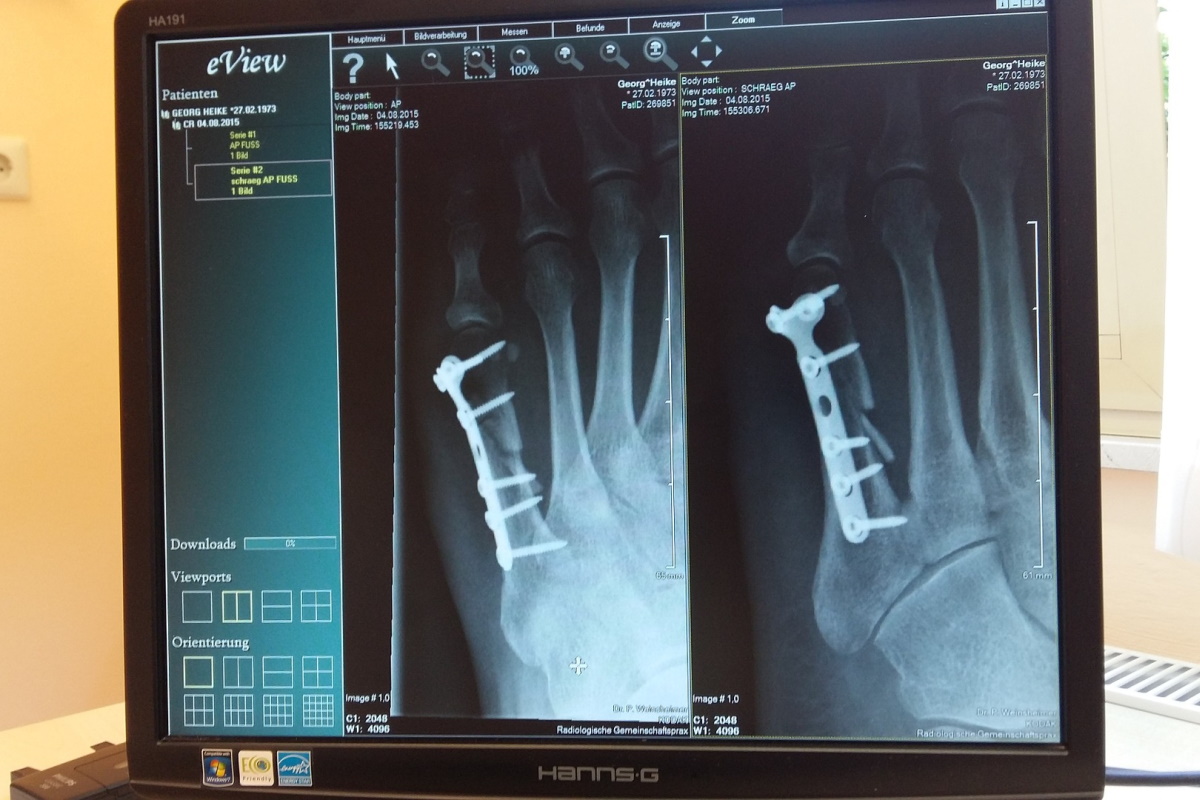

Фото: pixabay/spinheike

Ряд врачей-ортопедов оказались замешаны в коррупционной схеме: продвигали за вознаграждение эндопротезы определенных иностранных фирм. Об этом сообщил заместитель начальника Следственного управления КГБ Константин Бычек.

– Отдельная категория врачей-ортопедов и руководителей белорусских учреждений здравоохранения, действуя в интересах иностранных коммерческих организаций, используя свое служебное положение, создавали условия для приобретения и установки белорусским пациентам эндопротезов конкретных иностранных производителей, – рассказал он в эфире СТВ.